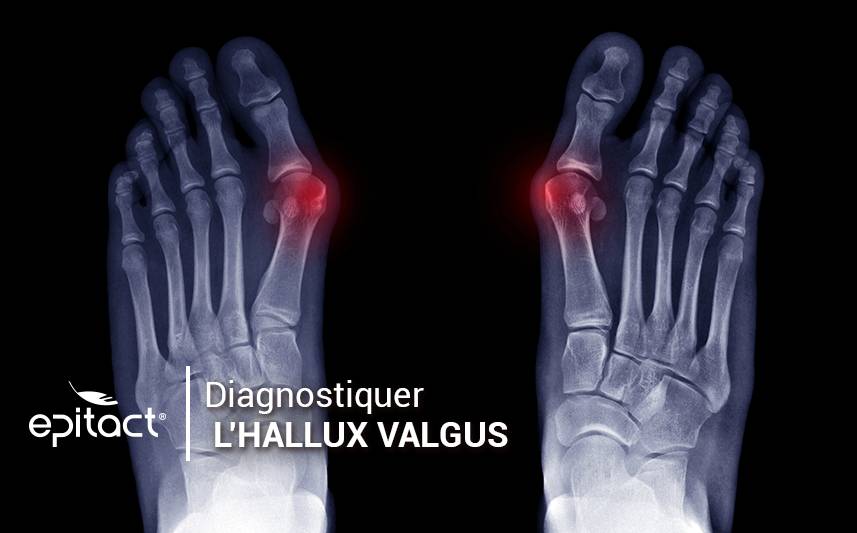

Bilan radiographique

Un bilan radiographique a pour but de confirmer le pré-diagnostic en cas d’hallux valgus. Il permet de visualiser avec précision l’angle de déviation. Le médecin dispose ainsi des éléments nécessaires pour étudier avec sérénité les éventuelles actions curatives et correctives.

Par ailleurs, les radiographies montrent les conséquences de la déviation de l’hallux sur les orteils voisins mais aussi sur la structure globale du pied. Une radio des deux pieds vus de dessus permet d’apprécier l’angle de la déformation. Plusieurs clichés sont à prendre pour déterminer quand opérer l’hallux valgus ou les alternatives à proposer. De plus, une radiographie des deux pieds en face dorso-plantaire (vue du dessus) en charge et en schuss, c’est-à-dire les genoux fléchis à 30°, est à effectuer.

Enfin, deux autres clichés sont nécessaires : un du pied nu, de profil et en charge, et un autre pour évaluer et visualiser les sésamoïdes (de face en charge, autrement appelé l’incidence de Guntz).